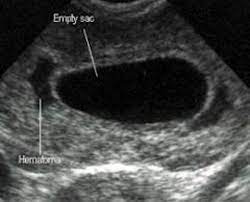

How Long Can An Anembryonic Pregnancy Last - ≥11 days after scan showing gestational sac with yolk sac, but no embryo, or 1.2.. In an anembryonic pregnancy or blighted ovum pregnancy, the sac develops, however, there is no foetus inside. Interestingly, a recent study found significantly fewer trophoblasts in women who had been diagnosed with ectopic pregnancy (an embryo attached outside the uterus) or blighted ovum. In anembryonic pregnancy, a blastocyst is formed from a fertilised ovum, but the fetal pole/embryonever develops, though histologically some fetal material can be demonstrated in most cases. Absent yolk sac when msd >8 mm on transvaginal ultrasound (tvus) 2. The patient may be asymptomatic, presenting for an early pregnancy ultrasound.

A blighted ovum occurs within the first trimester, often before a woman knows she is pregnant. See full list on mayoclinic.org Your body realises the pregnancy is not developing properly and starts to shed blood and tissue from the uterus. If you experience multiple consecutive miscarriages, talk with your doctor or other care provider to identify any underlying causes. An ultrasound will show an empty gestational sac. What are the signs and symptoms of anembryonic pregnancy? A pregnancy test may be positive because the early embryo secretes a pregnancy hormone human chorionic gonadotropin (hcg) until the embryo stops developing and fails to implant. See full list on mayoclinic.org Because a blighted ovum still makes hormones, it can show up as a positive pregnancy test. In anembryonic pregnancy, a blastocyst is formed from a fertilised ovum, but the fetal pole/embryonever develops, though histologically some fetal material can be demonstrated in most cases. See full list on mayoclinic.org May 19, 2020 · about 15 percent of all pregnancies end in miscarriage before 13 weeks of pregnancy. ≥11 days after scan showing gestational sac with yolk sac, but no embryo, or 1.2.

Mar 01, 2018 · natural expulsion may take up to two weeks. A blighted ovum eventually results in miscarriage. An ultrasound will show an empty gestational sac. A blighted ovum will cause a miscarriage usually at 7 to 12 weeks of pregnancy. May 19, 2020 · about 15 percent of all pregnancies end in miscarriage before 13 weeks of pregnancy. In an anembryonic pregnancy, however, the trophoblast attaches itself to the uterus, but the blastocyst never fully forms. Due to falling hcg levels, the clinical signs of pregnancy tend to subside. When there is no embryo seen on endovaginal scanning in a gestational sac with mean sac diameter (msd) ≥25 mm 4 or 1.

An ultrasound will show an empty gestational sac. A blighted ovum usually occurs early in pregnancy between about week 8 and week 13 sometimes before you even know you're pregnant. See full list on mayoclinic.org What are the signs and symptoms of anembryonic pregnancy? Alternatively, she may present with vaginal bleeding in early pregnancy. If you experience multiple consecutive miscarriages, talk with your doctor or other care provider to identify any underlying causes. Absent yolk sac when msd >8 mm on transvaginal ultrasound (tvus) 2. See full list on radiopaedia.org